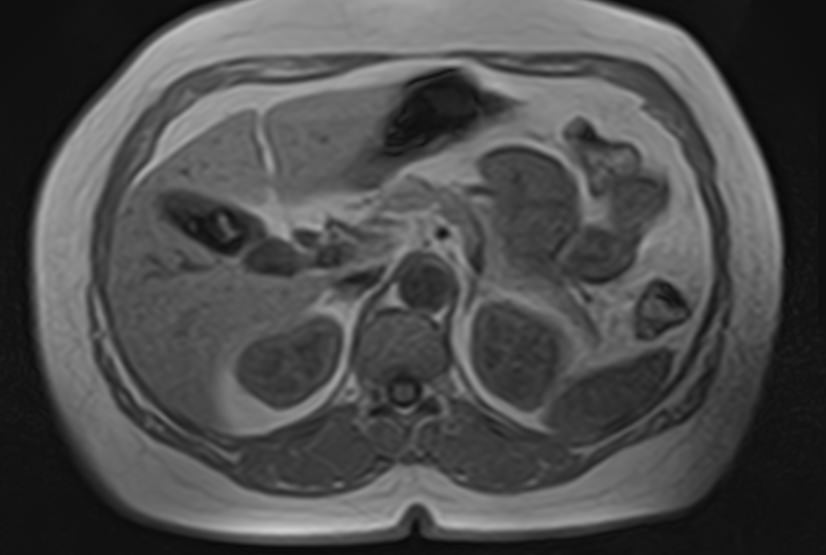

Магнитно-резонансная томография является наиболее точным и информативным методом обследования надпочечников с целью выявления различных заболеваний. Клиника «Доступная медицина» располагает новейшим томографом экспертного уровня TOSHIBA VANTAGE TITAN 1,5 Тесла, который обеспечивает высокую точность и достоверность результатов исследования.

Методика подразумевает послойное сканирование анатомической зоны надпочечников с последующей цифровой обработкой полученных данных для создания трехмерных изображений. Для более детальной визуализации патологических очагов, особенно при подозрении на развитие опухолевых образований, применяется контрастное усиление.